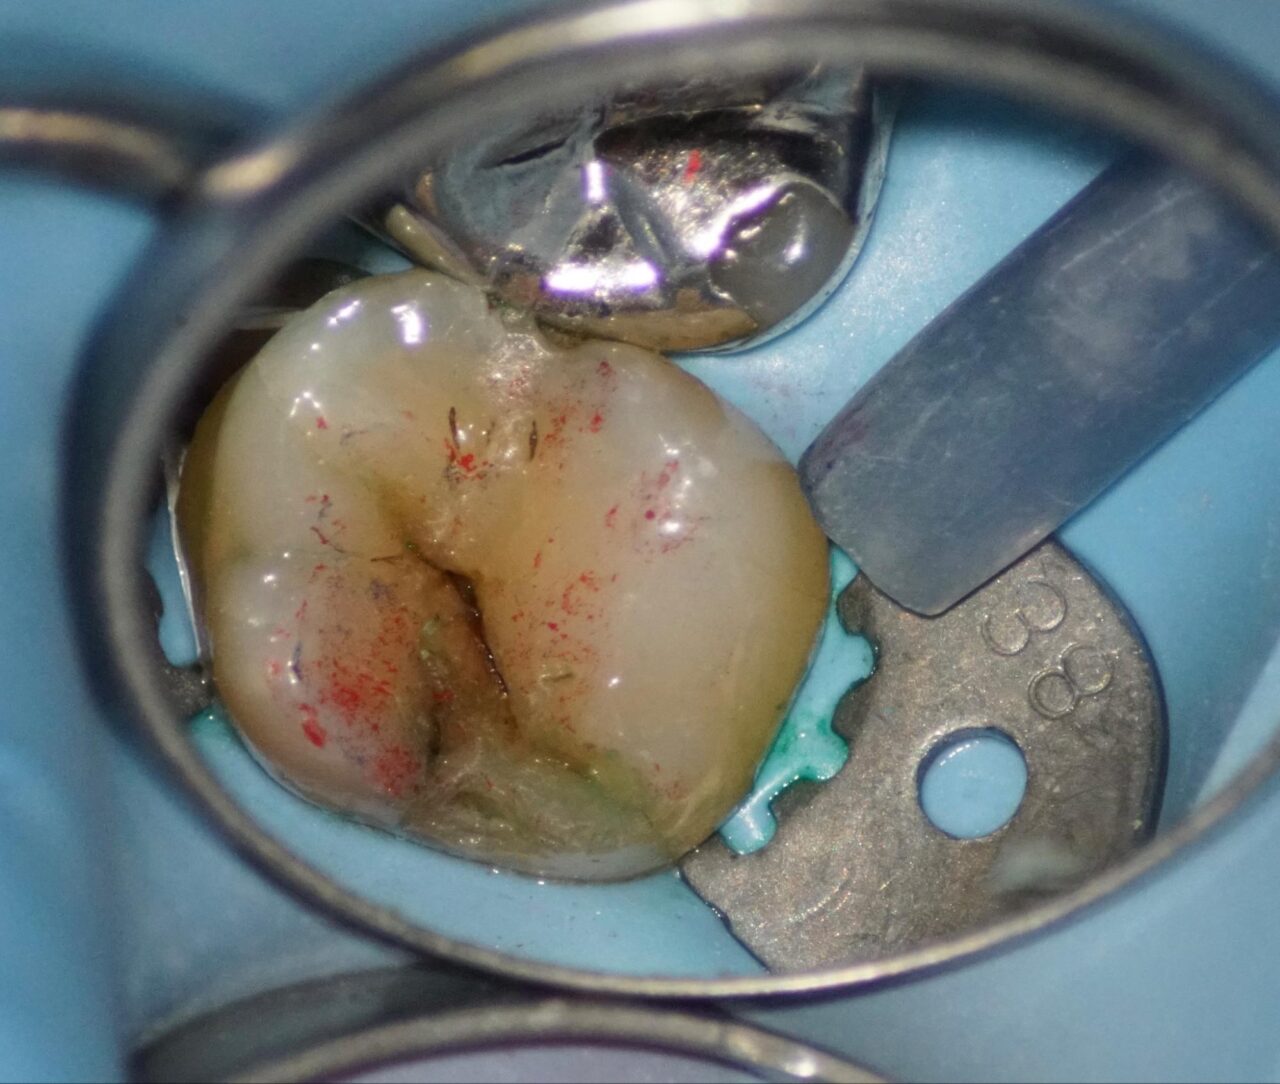

麻酔を行い、ラバーダム防湿時の写真。

まず口蓋側の咬合面を削合するとクラックラインが明確になってきました。

さらに頰側咬合面を削合すると遠心部から近心部のクラックライン、咬合面を斜めにわたる深いクラックラインが確認する事ができる。

クラックラインに沿って慎重に削合していくと、歯髄に近くなって内部のピンク色が視えてくる。

クラックラインを削っていくと歯髄に交通してしまいました。